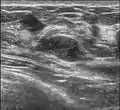

Since both fibroadenomas and breast lumps as a sign of breast cancer can appear similar, it is recommended to perform ultrasound analyses and possibly tissue sampling with subsequent histopathologic analysis in order to make a proper diagnosis. Unlike typical lumps from breast cancer, fibroadenomas are easy to move, with clearly defined edges.[1][2]

A fibroadenoma is usually diagnosed through clinical examination, ultrasound or mammography, and often a biopsy sample of the lump.[8] Suspicious findings on imaging may result in a person needing a biopsy in order to gain a definitive diagnosis. There are three types of biopsies: fine-needle aspiration, core-needle biopsy and surgical biopsy. The method of biopsy depends on the appearance, size and location of the breast mass.[18]

The FDA approved cryoablation of a fibroadenoma as a safe, effective, and minimally-invasive alternative to open surgical removal in 2001.[25] During cryoablation, ultrasound imaging is used to guide a probe into the mass of breast tissue. Extremely cold temperatures are then used to destroy the abnormal cells, and over time the cells are reabsorbed into the body.[26] The procedure can be performed as an outpatient surgery using local anesthesia, and leaves substantially less scarring than open surgical procedures and no breast tissue deformation.